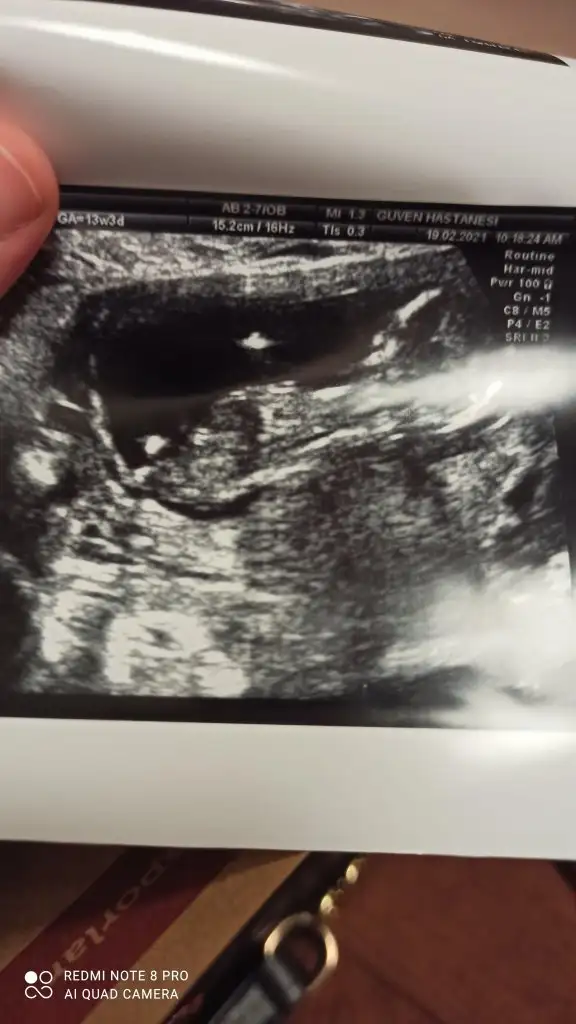

Bundan bahsetmiyorum. Bir sonrakinde kesin konuşacağı sözlerden bahsediyorum.“Açısından emin olamadım kız gibi ama erkeğe de benziyor %65 erkek olabilir ama net değil” doktorumun kurduğu cümle![]()

12. Hafta karın ultrason lütfen tahminnKız sanki emin olamadım 12-13 hafta olursa paylaşın![]()

Genital organlar 14. haftadan sonra tamamlanmaya başlıyor. Öyleki nadiren de olsa 11. haftada bile cinsiyet görenler var. Kesin terimler kullanıp durmayın. Kız bebeğe oğlan, oğlan bebeğe kız diyorsunuz gibime geliyor sanki...Testisimiilerleyen haftada oluşur 16-18 de

Bu bebiş de kız benceBanada tahminde bulunur musunuz 12+2